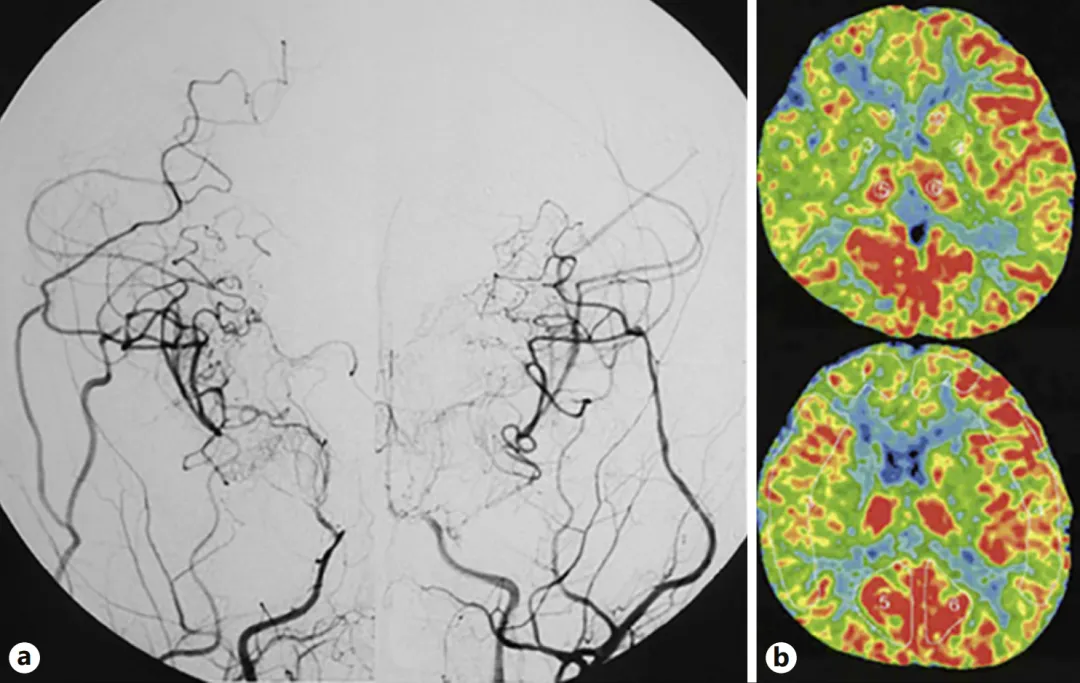

圖a:第二次手術半年后,雙側頸內動脈血管造影顯示側支血管網(wǎng)絡發(fā)育良好,基底煙霧血管消退。    圖b:雙側腦血流顯示有所改善。

圖a:第二次手術半年后,雙側頸內動脈血管造影顯示側支血管網(wǎng)絡發(fā)育良好,基底煙霧血管消退。

圖b:雙側腦血流顯示有所改善。